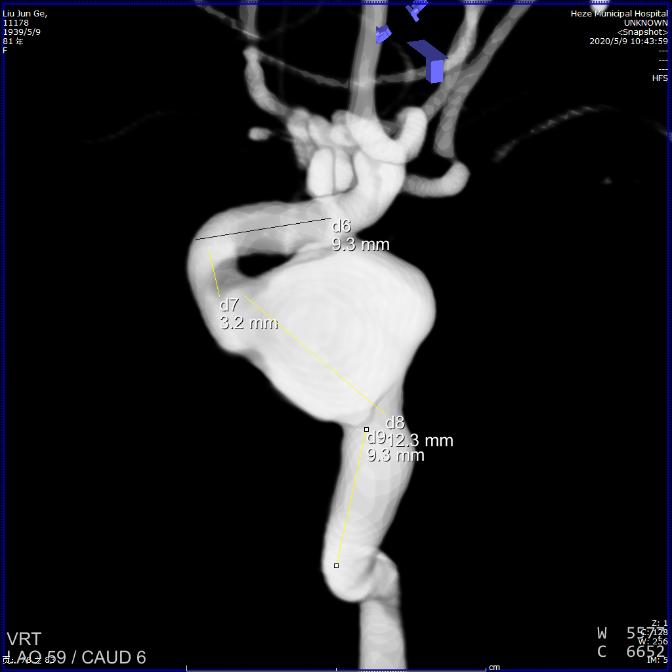

术前影像

术前测量:动脉瘤大小为12x11mm,瘤颈为13mm,动脉瘤远端血管直径3.8mm,近端血管直径4.5mm。